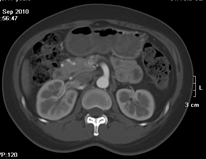

如上圖所示,相鄰的三張軸位圖像未見(jiàn)明顯異常,根據(jù)傳統(tǒng)軸位圖像很難得到準(zhǔn)確的臨床診斷。

同一病人利用容積數(shù)據(jù)進(jìn)行三維處理后,高品質(zhì)MPR和三維圖像上則清晰顯示了縱向排列的腹腔干與腸系膜上動(dòng)脈相鄰近,血管發(fā)生變 異,近端血管閉塞,為臨床提供了精確的診斷信息。